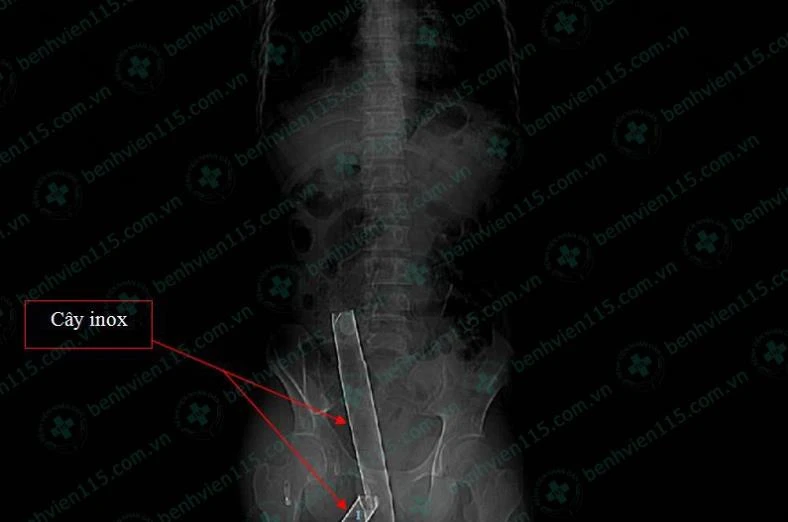

Cây inox xuyên qua mông anh T. Ảnh: BV CUNG CẤP

Kết quả chụp CT-scan ghi nhận cây inox chẳng những gây tổn thương mô mềm mà còn làm gãy một số xương trong quá trình anh T. di chuyển tới BV.

Các bác sĩ (BS) nhanh chóng phẫu thuật mở ổ bụng và rút cây inox ra ngoài. Cây inox dài 1,1m, đường kính 3cm, đoạn xuyên thấu vào anh T. khoảng 25cm.